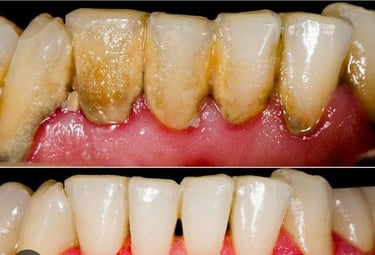

soins parodontaux

Soins des gencives et prévention du déchaussement dentaire.

Pour une bouche saine et un sourire durable.